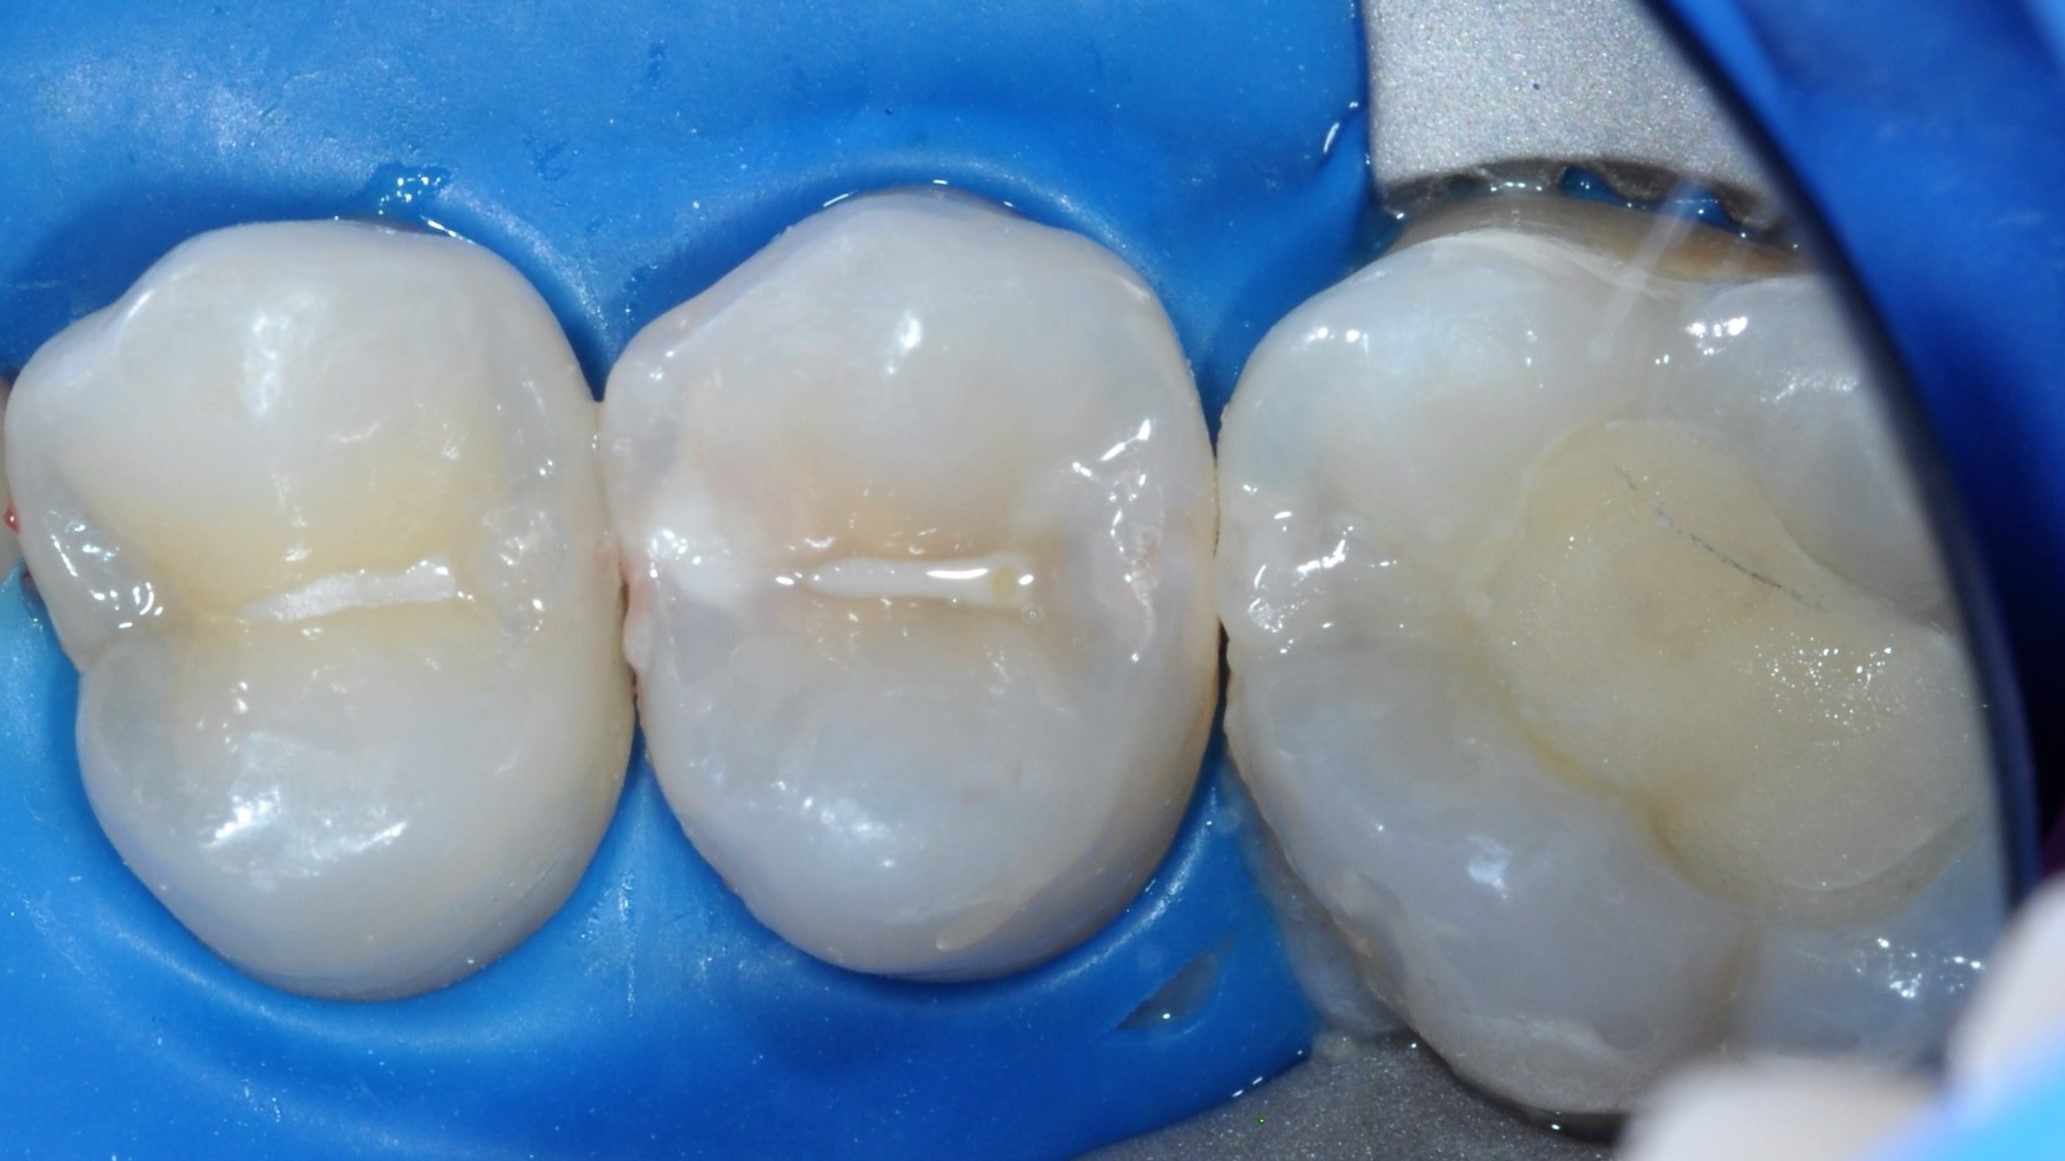

Leczenie zachowawcze zęba 15 rozpoczęto od testu żywotności (reakcja na bodziec zimny prawidłowa). Wykonano znieczulenie nasiękowe oraz izolację pola zabiegowego koferdamem (Rubber-Dam, Cerkamed) (ryc. 1). Ubytek opracowywano zgodnie z wytycznymi Europejskiego Towarzystwa Endodontycznego (European Society of Endodontology – ESE) w sprawie leczenia próchnicy głębokiej i obnażeń miazgi (1). W pierwszej kolejności, w powiększeniu, przy użyciu mikroskopu, wiertłem diamentowym na końcówce przyspieszającej usunięto próchnicowo zmienione szkliwo. Następnie wiertłem różyczkowym na mikrosilnik usunięto zainfekowaną bakteryjnie zębinę na peryferiach ubytku (infected dentine, soft dentine). Zbliżając się do komory zęba, zmieniono wiertło na sterylne i na niskich obrotach usuwano kolejne partie zębiny zainfekowanej. Podczas końcowej fazy opracowania ubytku doszło do próchnicowego obnażenia miazgi (obnażenie miazgi klasy II według ESE) (1) (ryc. 2). Zębinę zdemineralizowaną (affected dentine, firm dentine) pozostawiono w dnie ubytku. Krwawienie z miejsca obnażenia zahamowano sterylną gąbką, nasączoną roztworem 0,9-procentowym NaCl, uciskając przez 5 minut. Obnażenie zaopatrzono materiałem na bazie MTA (BIO MTA +, Cerkamed) i pozostawiono do wstępnego związania przez 12 minut (ryc. 3).

Ryc. 1. Sytuacja początkowa.